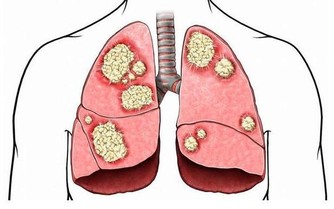

*****六、男性乳房突出*****

原因:如果男性乳房突出是由於體重超重所引起的,方法很簡單:吃得健康、經常鍛煉和增長肌肉即可。

辦法:對於一些男性來說,乳房組織擴張(也被稱為男性乳房發育症)是由於睪丸激素分泌量減少和雌激素分泌量增加所引起的。一些藥物和草藥會引起男性乳房發育,某些嚴重的疾病(如癌症、甲狀腺亢進或激素功能紊亂)也會起到影響。因此一旦出現這種癥狀,應當及時就醫。